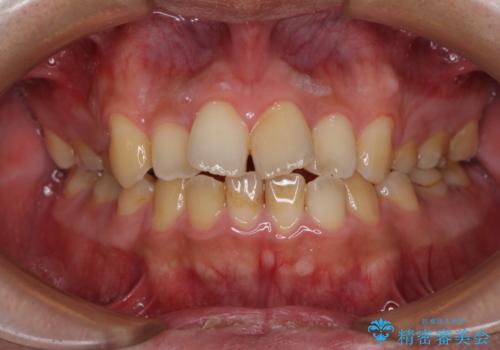

後戻りでデコボコの前歯 インビザライン矯正治療

- 高校時代に行った抜歯矯正が後戻りをしたとのことで来院された患者様です。

再矯正であることから、目立ちにくい装置を希望されたため、インビザラインにて矯正治療を行うこととしました。